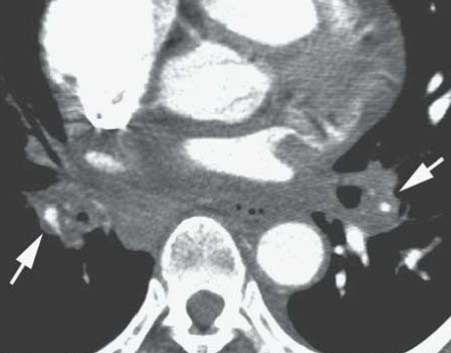

CT

- Masse médiastino-hilaire (peut être calcifiée)

- Comblement des espaces graisseux

- ADP calcifiées (si infection histoplasmose)

- Rétrécissement trachéo-bronchique

- Retrecissement des vaisseaux